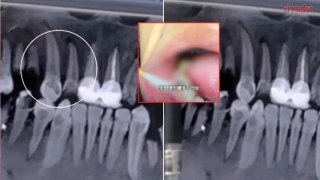

หนุ่มช็อค!!! น้ำอัดลม ทำฟันร่วงหมดปาก สาเหตุเกิดจากอะไร???

ต้องยอมรับว่า น้ำหวาน น้ำอัดลม เป็นสิ่งที่ขาดไม่ได้ เพราะเป็นสิ่งเติมความสดชื่นให้กับทุกเพศทุกวัย ยิ่งในวันที่อากาศร้อน ๆ หรือวันเหนื่อย ๆ น้ำตาลที่ผสมจะช่วยให้ผู้ดื่มสดชื่นมากขึ้น ฟัง ๆ ดู ก็เหมือนว่าจะมีแต่ข้อดี แต่เปล่าเลย เราก็มักรู้กันอยู่แล้วว่าน้ำอัดลมนั้นมีโทษมากมาย ที่แน่ ๆ 8 โทษนี้ ได้แก่ 1. ขาดวิตามิน 2. ฟันสึกกร่อน 3. โรควิตกกังวล 4. โรคอ้วน 5. ปัญหาเรื่องผิว 6. ปัญหาเกี่ยวกับหัวใจและ.. ดูเพิ่ม